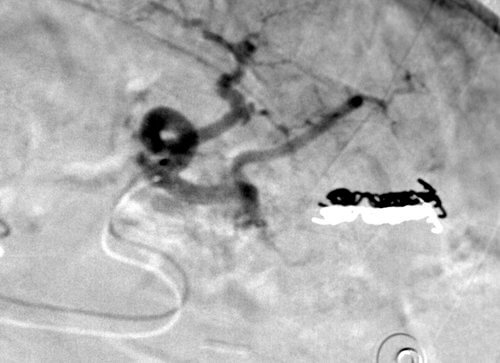

29 year old male s/p motorcycle accident with a splenic laceration.

Comment: This, like case #3, is another example of a splenic laceration with active extravasation. Once again, we tried and were able to selectively catheterize the injured artery, enabling performance of a distal embolization.